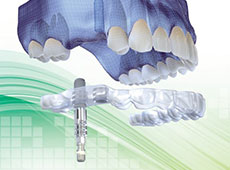

サージカルステントはインプラントを埋入する際のヒューマンエラーを防ぐ埋入ガイドです。これにより安全に、確実にインプラント埋入手術を行う事ができます。サージカルスラントは必要に応じて作成します。

血管や神経の位置、骨量を正確に把握するため、当院では3Dによるインプラントシミュレーションを行います。通常のレントゲンでは撮影出来なかった箇所を把握出来る事により、より安全な埋入手術が可能になります。

サージカルステント・3Dシミュレーションはインプラント価格に含まれています!